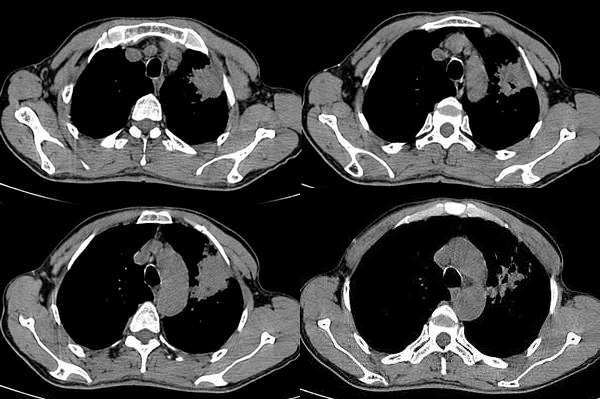

男,58岁,咳嗽1月加重1周,伴痰中带血

左肺上叶胸膜下不规则团块阴影,内见空泡,边缘光整,肺纵比率>50%,支持左肺癌的诊断。

ct:左上肺块状影、其内徐点状气体外蜜度大致均匀。周围粗大索状影

其内透光影仔细观察像是支气管,病灶周围有渗出改变,该病灶不考虑感染性病变,机化性肺炎能排除吗

理由:1 病灶有恶性肿瘤的特征:空泡征,毛刺,棘状突起

左上肺病灶与胸膜脂肪线存在,未见明显胸膜凹陷征,虽然病灶边缘不规则,但未见明显“短毛剌、切迹征、免耳征、血管束集征”,其间亦见条索状、斑点状影,认为左上肺结核或炎性病变>周围型肺癌。

病灶比较虚 周围有明显渗出 卫星灶及条素影 病灶边缘有棘突 胸膜外脂肪层存在考虑结核

考虑肺结核可能性大。理由1.病灶形态不规则,其周有卫星灶,2.病灶没有毛刺征,灶周出现粗大索条影.